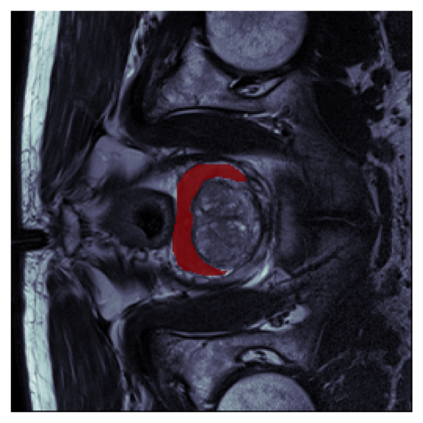

The sigmoid activation is the standard output activation function in binary classification and segmentation with neural networks. Still, there exist a variety of other potential output activation functions, which may lead to improved results in medical image segmentation. In this work, we consider how the asymptotic behavior of different output activation and loss functions affects the prediction probabilities and the corresponding segmentation errors. For cross entropy, we show that a faster rate of change of the activation function correlates with better predictions, while a slower rate of change can improve the calibration of probabilities. For dice loss, we found that the arctangent activation function is superior to the sigmoid function. Furthermore, we provide a test space for arbitrary output activation functions in the area of medical image segmentation. We tested seven activation functions in combination with three loss functions on four different medical image segmentation tasks to provide a classification of which function is best suited in this application scenario.